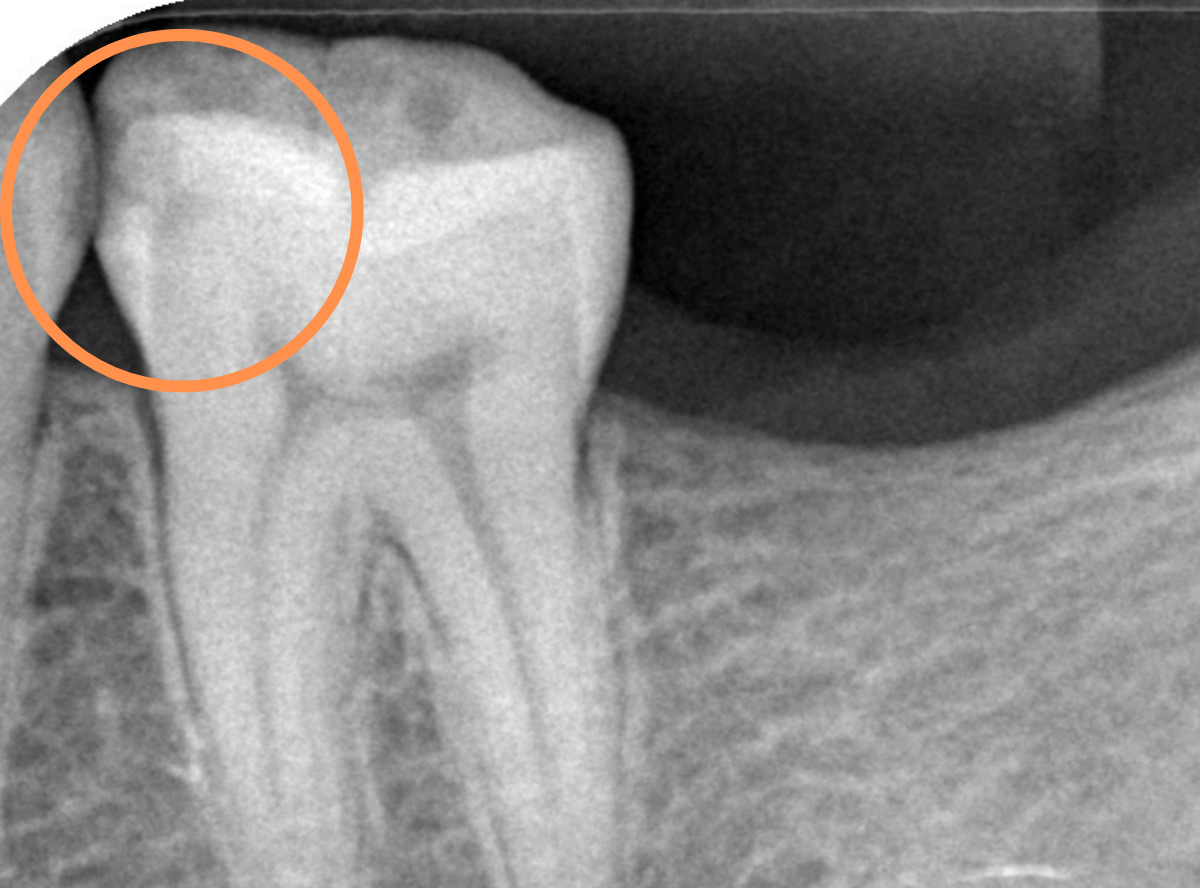

Case.26 <動画編> 症状もなく、深く進行する「歯と歯の間の虫歯治療」

今回は、歯と歯の間で大きな虫歯が進行しているケースです。

見た目に虫歯は見当たらず、痛みもありませんが、レントゲン写真で確認すると、歯と歯の間から、歯の神経まで達するほど虫歯が広がっています。

これほど大きな虫歯でも、症状がない事は多くあります。

症状がないから、「自分は虫歯はない」と考える方もいますが、そんな事はありません。

虫歯は、ある日突然進行する事はなく、このように症状がないまま深く進行し、急に痛みを感じる事も多いです。

痛みを感じてからの治療の多くは、神経を除去する治療になり、治療期間は長くなり、歯の寿命も短くなってしまいます。

定期メンテナンスで、早期発見・早期治療するようにしましょう。